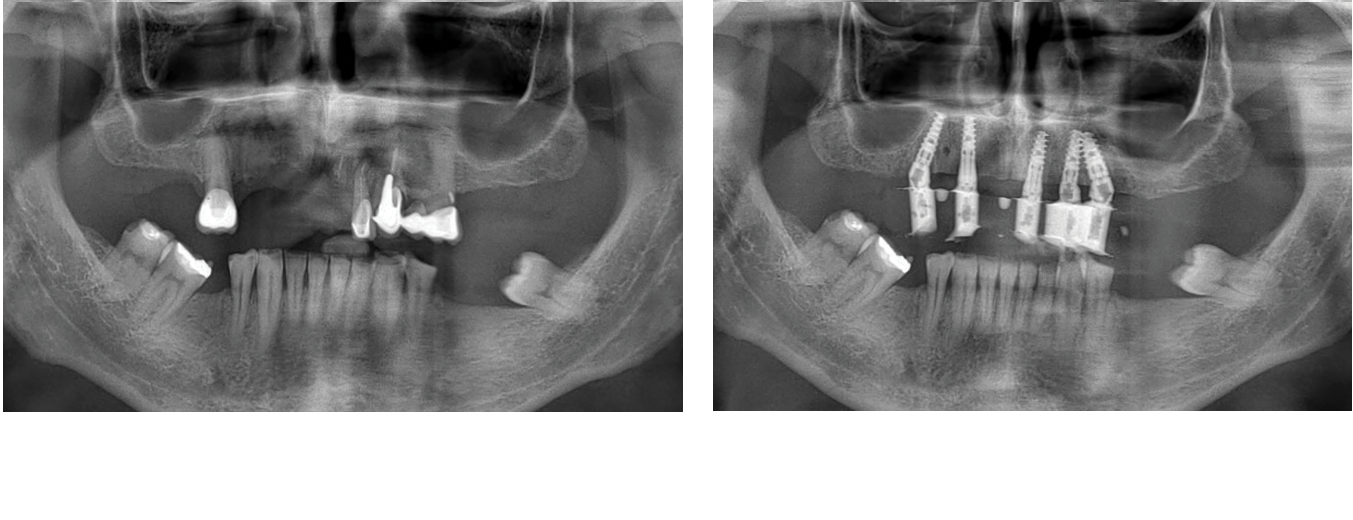

Join a small group of experienced clinicians for an intensive hands-on program where you’ll place 15+ implants on real patients under expert supervision.

Train in both free-hand and guided techniques while mastering diagnosis, planning, bone biology, and soft tissue management.

Join an elite group of clinicians for a 3-day immersive program where you’ll treat 3 full arch patients using state-of-the-art techniques: free-hand, guided surgery (flapless), and stackable guides with bone reduction.